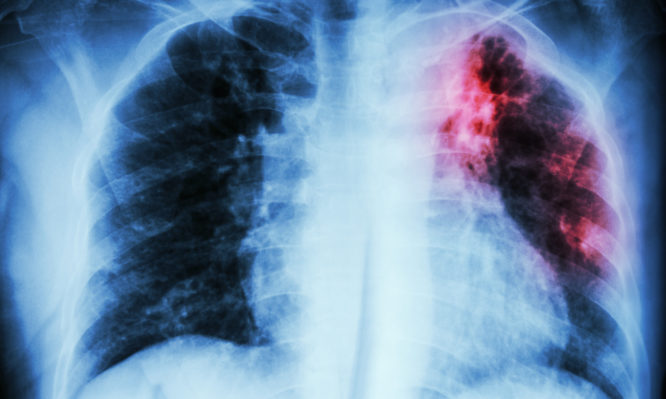

Προσθέτει ότι οι ασθενείς με φυματίωση είναι ιδιαίτερα ευάλωτοι, καθώς συχνά φέρουν μόνιμες πνευμονικές βλάβες που επιδρούν αρνητικά στους φυσιολογικούς αμυντικούς μηχανισμούς του αναπνευστικού συστήματος, και προδιαθέτουν σε άλλες λοιμώξεις. Η φυματίωση αποτελεί σταθερά την πιο θανατηφόρα λοιμώδη νόσο παγκοσμίως. Περίπου 1.5 εκατομμύριο ασθενείς κατέληξαν από τη νόσο το 2018 με βάση τα επίσημα στοιχεία του ΠΟΥ, ενώ περίπου 10 εκατομμύρια ασθενείς νοσούν ετησίως.

Οι ασθενείς με χρόνιες πνευμονικές βλάβες λόγω παλαιάς θεραπευθείσας φυματίωσης (π.χ. βρογχιεκτασίες), που μπορεί να χρήζουν μόνιμης οξυγονοθεραπείας στο σπίτι, θα πρέπει να αποφεύγουν τον συγχρωτισμό με πολλά άτομα για αποφυγή έκθεσης σε ασυμπτωματικούς φορείς του ιού. Όταν εμφανίζουν συμπτώματα όπως πυρετό, βήχα, δύσπνοια, θα πρέπει να βρίσκονται σε στενή παρακολούθηση από πνευμονολόγο, και επί επιδείνωσης των συμπτωμάτων ή της οξυγόνωσης του αίματος να παραπέμπονται στα κέντρα αναφοράς COVID-19.